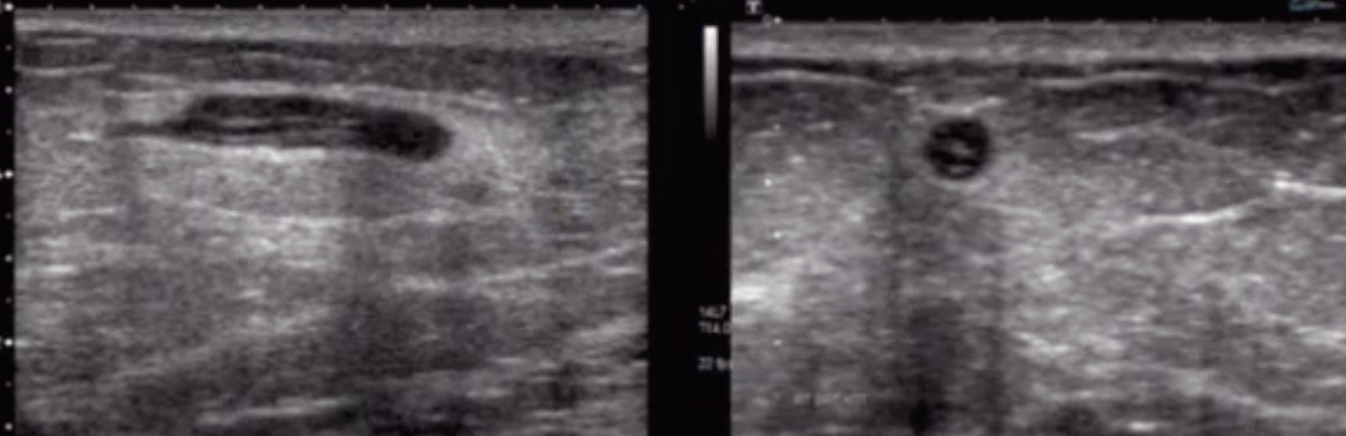

Mondor’s

• Tubular looking thing

• May have some doppler flow

• Tender palpable cord

• This is a thrombosed superficial vein

• No need for AC